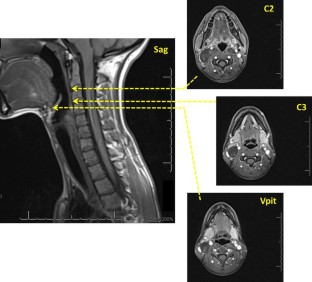

Age-related loss of muscle bulk and strength (sarcopenia) is often cited as a potential mechanism underlying age-related changes in swallowing. Our goal was to explore this phenomenon in the pharynx, specifically, by measuring pharyngeal wall thickness and pharyngeal lumen area in a sample of young versus older women. MRI scans of the neck were retrospectively reviewed from 60 women equally stratified into three age groups (20s, 60s, 70+). Four de-identified slices were extracted per scan for randomized, blinded analysis: one mid-sagittal and three axial slices were selected at the anterior inferior border of C2 and C3, and at the pit of the vallecula. Pixel-based measures of pharyngeal wall thickness and pharyngeal lumen area were completed using ImageJ and then converted to metric units. Measures of pharyngeal wall thickness and pharyngeal lumen area were compared between age groups with one-way ANOVAs using Sidak adjustments for post-hoc pairwise comparisons. A significant main effect for age was observed across all variables whereby pharyngeal wall thickness decreased and pharyngeal lumen area increased with advancing age. Pairwise comparisons revealed significant differences between 20s versus 70+ for all variables and 20s versus 60s for all variables except those measured at C2. Effect sizes ranged from 0.54 to 1.34. Consistent with existing sacropenia literature, the pharyngeal muscles appear to atrophy with age and consequently, the size of the pharyngeal lumen increases.

Fig. 2